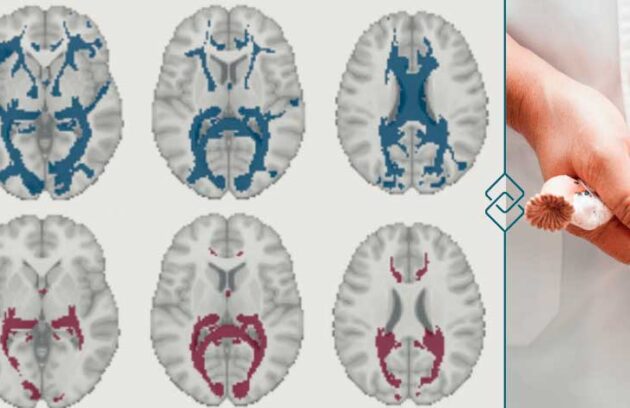

Você sabia que o ciclo menstrual pode afetar o cérebro? Pesquisadores notaram mudanças significativas devido aos hormônios. Veja!